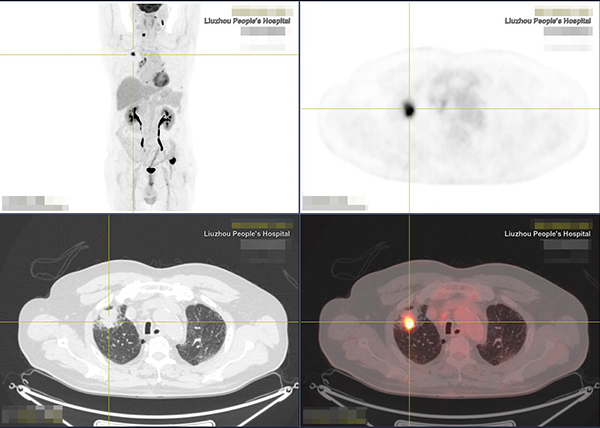

就在這時,醫生介紹了一個評價分期的利器:PET/CT。通過PET/CT全身掃描成像,結果顯示文老伯右肺上葉周圍型肺癌,雙側頸部、縱隔及肺門多發淋巴結轉移,第6頸椎椎體、第8胸椎右側橫突、左側第8后肋、左側髂骨多發骨轉移。了解全身情況后,醫生運用PET/CT的檢查結果指導穿刺活檢,精準選擇最佳活檢部位,提高活檢準確率,穿刺結果顯示腸型腺癌,低分化區30%,高分化區70%,為臨床醫生提供了全面精細的疾病診治依據。

“早期腫瘤未發生解剖結構變化,傳統的CT、MR檢查均難以發現病變。但腫瘤細胞代謝活躍,PET通過對人體注射18F標記的脫氧葡糖,使病變區域出現異常“濃聚”,圖像上表現為突出‘光點’,結合CT解剖成像,就能較早發現隱藏的腫瘤,精準判斷腫瘤的良惡性,堪稱探測腫瘤的雷達,可真正實現腫瘤的‘早發現、早診斷、早治療’。” 柳州市人民醫院放射科副主任鄧奎品說,“PET/CT在腫瘤的早期定位、定性、分期、復發監測、靶區勾畫、腫瘤療效監測等方面具有重大意義,能為臨床診斷提供更高效、更全面、更精準的影像學支持,為患者提供高科技、高品質診療服務。”